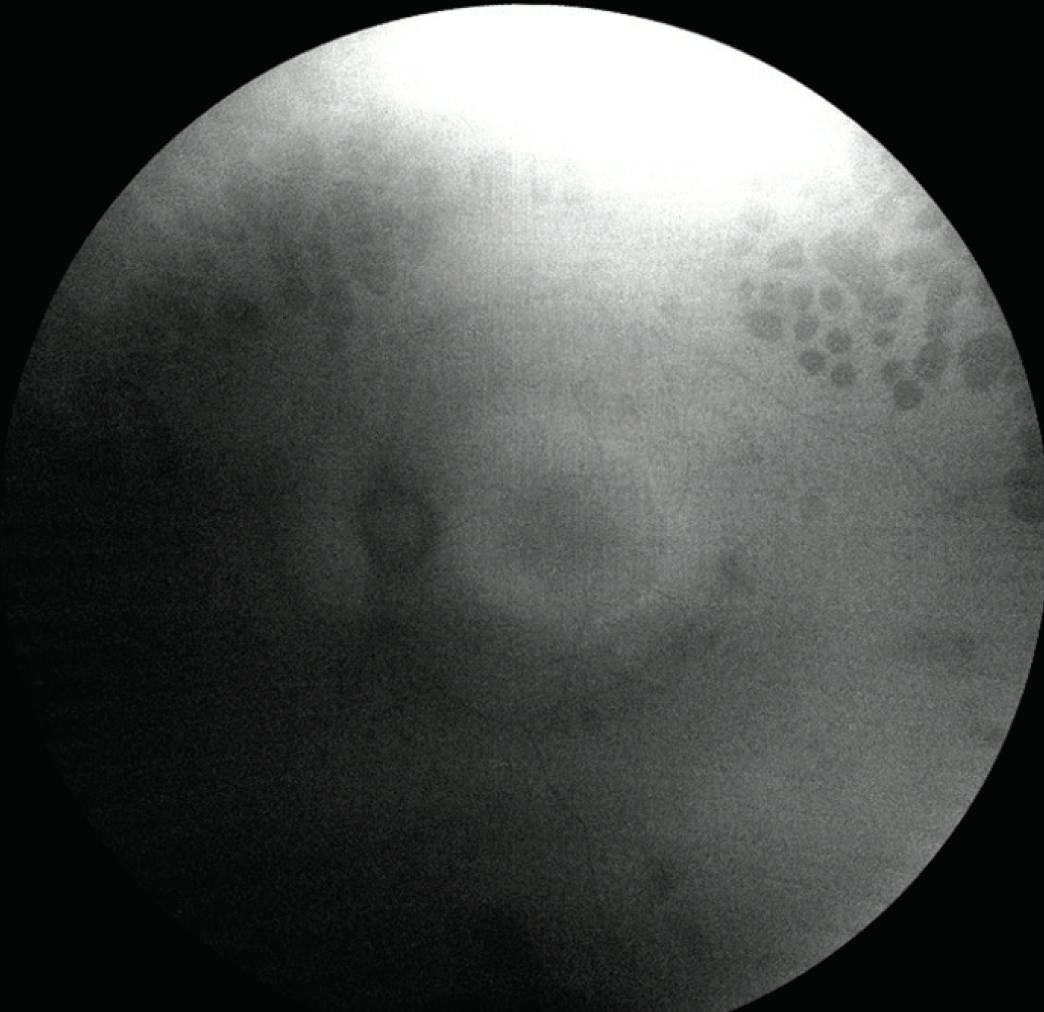

A 51-year-old woman with a history of HIV, well controlled on highly active antiretroviral therapy, presented with right-eye redness and pain for 1 day. Her VA was light perception OD and 20/60 OS, which she stated was her baseline. On examination of the right eye, she exhibited 1+ pigmented cell in the anterior chamber, a pale nerve, and retinal changes noted in Figure 2A. In the left eye, she had superior prior laser scars and retinal changes noted in Figure 2B. OCT imaging revealed several findings, including outer retinal loss in the peripheral macula of the left eye (Figure 3). FAF was of poor quality in the right eye but demonstrated a hyperautofluorescent macular ring in the left eye (Figure 4). She had last been seen 10 years prior, at which time she underwent fundus imaging and a full infectious/inflammatory workup that was negative aside from known HIV.

<p>Figure 3. OCT imaging showed foveal dragging with subretinal fibrosis, subretinal fluid, and diffuse outer retinal loss in the right eye (A). The left eye showed peripheral outer retinal loss with a preserved photoreceptor layer centrally, CME, and an early lamellar hole/large cyst in the fovea (B).</p>

Figure 3. OCT imaging showed foveal dragging with subretinal fibrosis, subretinal fluid, and diffuse outer retinal loss in the right eye (A). The left eye showed peripheral outer retinal loss with a preserved photoreceptor layer centrally, CME, and an early lamellar hole/large cyst in the fovea (B).